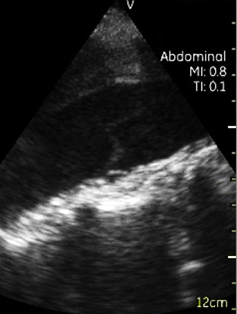

Vscan临床图片 腹部